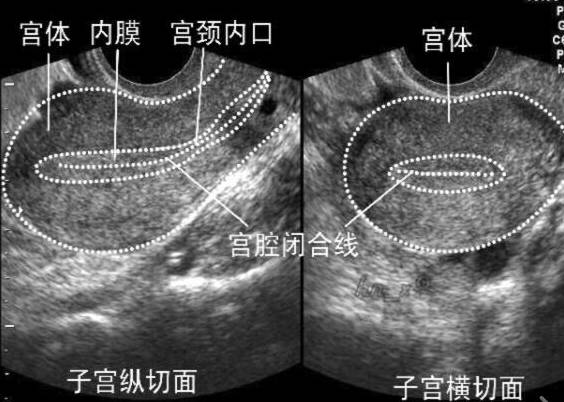

经常有病人在月经刚结束时来医院做超声后问:“医生,你帮我看看我的内膜是不是太薄了,不容易怀孕呀?!”问的人多了,让我意识到有必要在这里为大家科普一下“子宫内膜”的问题。

在怀孕的过程中,卵子就是“种子”,子宫内膜就是“土壤”。

只是这种“土壤”并非一成不变,在一个月内,月经的不同时期,子宫内膜的厚度也是有所不同的。

子宫内膜的厚度是随卵巢的排卵周期性变化而变化的(月经的不同时期:如卵泡早期、排卵期、黄体期,内膜的厚度各不相同)。

以一个月经周期30天,每次月经经期3-5天的女性举例,月经刚干净的时候内膜可能只有4mm;等到优势卵泡直径长到13mm左右,内膜长到7mm也是正常的;排卵期左右(月经第16天左右)内膜长到10mm也是正常的。

在卵泡早期的时候,由于优势卵泡还没有发育,绝大多数人的子宫内膜厚度都偏薄,3-5mm都是正常。

随着卵泡的不断增大,子宫内膜也不断增厚,排卵后内膜也不会迅速变薄,一般维持在8-15mm,过薄过厚都不好。

对于卵泡长大了,但内膜薄的女性,医生会给予雌激素口服增长内膜,一般排卵期左右的子宫内膜厚度为8—15mm,排卵期左右的子宫内膜低于6mm妊娠率会显著下降。